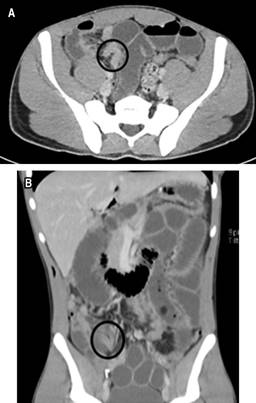

Se ingresó paciente para observación, hidratación por vía intravenosa con solución Ringer lactato y manejo médico sintomático persistiendo con sintomatología, por lo cual se indicó colocación de una sonda nasogástrica (SNG) y una tomografía computarizada (TC) de abdomen con contraste intravenoso. La TC de abdomen demostró obstrucción de intestino delgado con sospecha de hernia interna (Figura 1). Basado en hallazgos clínicos y radiológicos, se decidió realizar una laparoscopia diagnóstica de emergencia. Se identificó como origen de la obstrucción un asa de intestino delgado herniada en el espacio preperitoneal a través de un defecto peritoneal (Figura 2). No se identificaron datos de sufrimiento de asa, por lo cual se redujo la hernia y posterior cierre del defecto del peritoneo con poliglactina 910 2-0 puntos cruzados.

Figura 1: Tomografía axial computarizada de abdomen con contraste intravenoso. Dilatación de asas intestinales de hasta 3.5 cm de calibre, formación de niveles hidroaéreos. Zonas de disminución de calibre en tipografía de íleon distal a nivel de fosa iliaca derecha (círculo). Distal a esta zona de transición se observa disminución de calibre de marco colónico. Líquido libre en hueco pélvico. A) corte axial. B) Corte coronal.